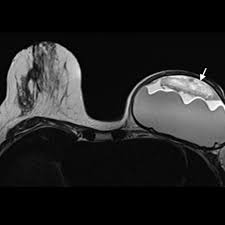

If you have silicone breast implants and suspect that an implant might have ruptured, talk to your plastic surgeon. When a rupture occurs your breast (s) will immediately deflate, usually within a day or two, and breast size will noticeably change. Nevertheless, your body will try to contain any silicone gel seeping in your breast tissue by forming a scar tissue around it, called "granulomas" or "siliconoma". Rupture can also cause capsular contracture. The relationship of free silicone to development or progression of disease is unknown. With silicone gel implants, you aren't able to physically see the appearance of a ruptured implant, whereas with saline implants, you will see a deflated breast with implant rupture. An imaging test, such as an mri or ultrasound, can show whether the implant has ruptured. What are the dangers of silicon? What is the life expectancy of silicone breast implants? Apr 01, 2019 · however, some may remain around the ruptured implant, and this can cause the fluid to change color. What are the risks of silicone implants? Silicone implant rupture that doesn't cause any noticeable symptoms is known as "silent rupture.". This makes is much more difficult to detect a rupture.

What is the life expectancy of silicone breast implants? An imaging test, such as an mri or ultrasound, can show whether the implant has ruptured. The saline will leak from the outer silicone elastomer shell of your implant. Nevertheless, your body will try to contain any silicone gel seeping in your breast tissue by forming a scar tissue around it, called "granulomas" or "siliconoma". Oct 29, 2020 · signs that your silicone implant has ruptured can include changes in breast shape and size, and increasing pain, firmness, and swelling over a period of weeks.

With silicone gel implants, you aren't able to physically see the appearance of a ruptured implant, whereas with saline implants, you will see a deflated breast with implant rupture. Light, clear fluid usually signals that the ruptured occurred within a month. Nov 14, 2013 · silicone breast implants can leak but do not deflate quickly the way saline implants do because the silicone gel is designed to stay in place when a leak occurs. An imaging test, such as an mri or ultrasound, can show whether the implant has ruptured. Changes in size or shape.

What happens if silicone breast implant ruptures? Oct 29, 2020 · signs that your silicone implant has ruptured can include changes in breast shape and size, and increasing pain, firmness, and swelling over a period of weeks. What are the dangers of silicon? Dark, yellow, straw colored fluid tends to indicate that the rupture has extended over several months. The relationship of free silicone to development or progression of disease is unknown. Rupture can also cause capsular contracture. Nevertheless, your body will try to contain any silicone gel seeping in your breast tissue by forming a scar tissue around it, called "granulomas" or "siliconoma". Nov 14, 2013 · silicone breast implants can leak but do not deflate quickly the way saline implants do because the silicone gel is designed to stay in place when a leak occurs. Silicone implant rupture that doesn't cause any noticeable symptoms is known as "silent rupture.". With silicone gel implants, you aren't able to physically see the appearance of a ruptured implant, whereas with saline implants, you will see a deflated breast with implant rupture. What are the risks of silicone implants? This makes is much more difficult to detect a rupture. Some patients experience symptoms of a silicone gel implant leak, including: